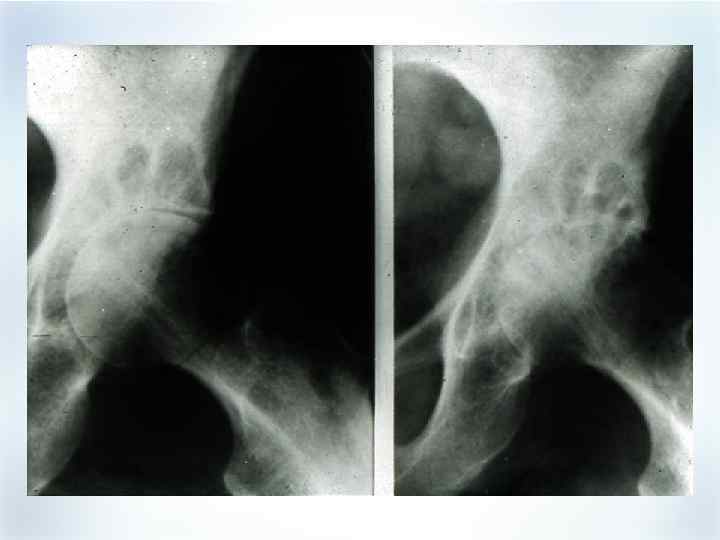

Прогрессирование деструкции за 7 лет болезни

Прогрессирование деструкции за 7 лет болезни